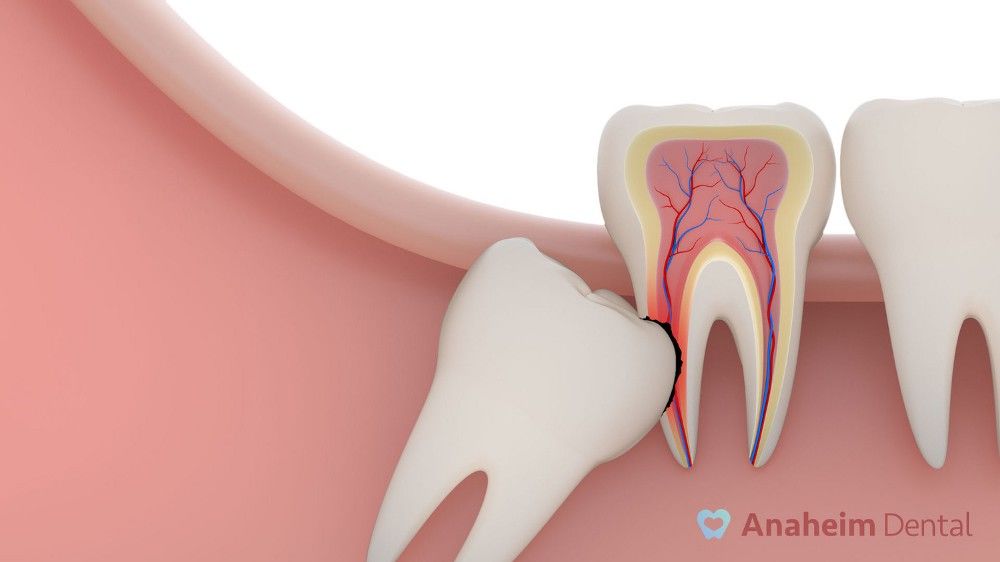

Хүн болгонд дөрвөн ширхэг агт араа шүд байх бөгөөд хоншоор ба эрүүний шүдний эгнээний хамгийн арын зайнд шүдлэдэг. Америкийн Шүдний Эмч нарын Холбооны мэдээллээр энэ шүд нь ихэнхдээ 17–21насанд шүдлэдэг. Америкийн Анестезиологи Эмч нарын Холбооны гишүүн Fred Quarnstrom эмч агт араа шүд нь цөөн тохиолдолд зөвхөн шүдний хэсэг нь л цухуйсан байдалтай тохиолддог бол ихэнхдээ шүдэлж гарч ирэлгүйгээр буйлан дотор үлддэг гэж тайлбарлаж байна. Ийнхүү буйлнаас цухуйлгүй яс болон бусад буйлны эдээр хучигдан үлдсэн агт араа шүдийг “саатсан агт араа” гэж нэрлэдэг.

Хүний түүхийн эрт үед хоол хүнс илүү хатуулаг байсан бөгөөд хатуу хоол хүнсийг байнга зажилсаны улмаас их араа шүднүүд яагаачгүй эрт элэгдэж дуусахад агт араа шүд түүний оронд урган гарч ирж үүргийг нь орлон гүйцэтгэдэг байсан байж болзошгүй гэсэн таамаглал байдаг. Гэтэл өнөө үед хоол хүнс зөөлөн болсоноор араа шүд элэгдэх асуудал үгүй болжээ. Үүний улмаас агт араа шүд ургах орон зай байхгүй болсон байна. Мөн түүнчилэн Fred Quarnstrom эмчийн батлаж байгаагаар орчин үеийн хүний эрүүний хэмжээ нь эрт үеийн хүмүүсийн эрүүний хэмжээнээс жижиг гэнэ.

Агт араа шүд ургах нь ихэнхдээ тэсвэрлэхийн аргагүй өвдөлт, буйлны шүдний орчмын халдварын голомт, буйлны үрэвсэл ба шүдний цооролтой хавсран явагддаг. Эдгээр өвчин эмгэг ба хүндрэлүүдийн зарим нэг нь агт араа шүд шүдний эгнээний хамгийн хойно байрлах учир угаахад хүндрэлтэй асуудалтай холбоотой байх нь бий. Иймд агт араа шүдийг угаахдаа зориулалтын урт бариултай нимгэн сойз ашиглах хэрэгтэй. Агт арааны бас нэг томоохон асуудал нь саатсан агт араа шүдний ойролцоо эрүүний ясанд уйланхай буюу киста байх явдал юм. Энэхүү киста нь эрүүний ясыг идэж хатингаршуулах бөгөөд мэдрэлийг дарж үрэвсүүлдэг.